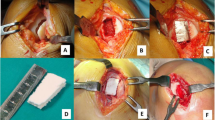

Among the developed osteochondral scaffolds, only three have currently been documented in clinical trials. TruFit® was the first one introduced in the clinical practice. It is a bilayer scaffold made of a semiporous poli-lactic (PLGA), poli-glycolic acid (PGA), and calcium sulfate biopolymer. The different size cylinders (from 5 to 11 mm and with a maximum depth of 18 mm) were initially introduced with the indication to backfill graft donor sites during OAT procedures, but they were later mainly used as a one-step osteochondral treatment [5]. MaioRegen is the most widely studied multi-layer scaffold. It is a nanostructured implant consisting of different ratios of collagen and hydroxyapatite organized in three-layers. The composition of this scaffold reproduces the extracellular matrix structures of cartilage and bone tissues and is based on the nucleation of hydroxyapatite nanocrystals onto self-assembled collagen fibers to generate a chemically and morphologically graded biomimetic material [71]. Initially, this scaffold was obtained from a square of 35 × 35 mm (manual sizing) with a depth of 6 ± 2 mm. Currently, the scaffold is available also in a cylindrical shape with different sizes (12—18 mm) and different depths (2 to 6 mm). Agili-C™ is the most recent osteochondral scaffold studied in the clinical practice. It is an aragonite-based scaffold consisting of two layers: a bone phase made of calcium carbonate in the aragonite crystalline form, and a superficial cartilage phase composed of modified aragonite and hyaluronic acid. This scaffold was developed in the shape of cylinders, with different sizes in terms of width and depth. Recently, a tapered version of the implants, with an angle of 2 degrees from the longitudinal axis, has been designed to improve the press-fit implantation of the cylinder [47].